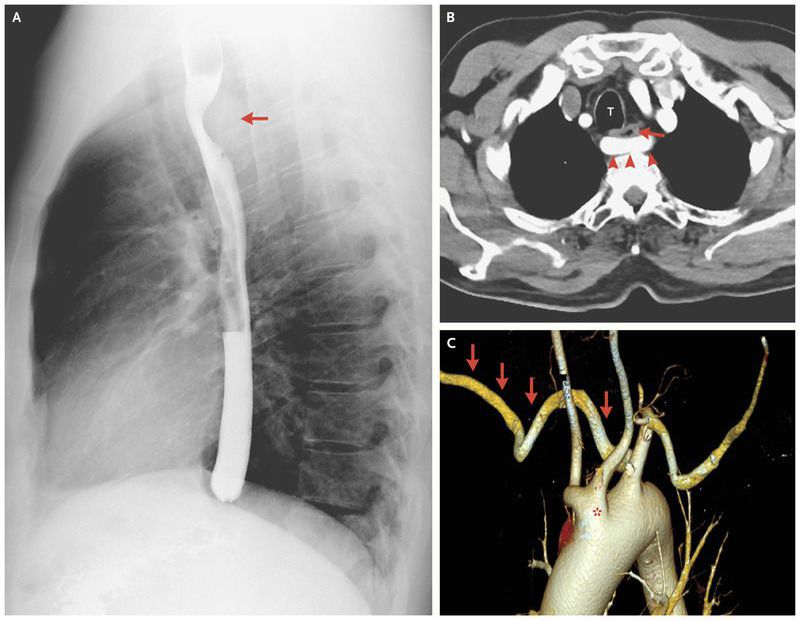

A 46-year-old otherwise healthy man presented with a 1-year history of occasional dysphagia to solid foods that was not accompanied by weight loss. The results of a physical examination were unremarkable. A barium-swallow examination revealed posterior oblique indentation of the proximal esophagus (arrow in Panel A and Panel B; T indicates the trachea in Panel B). A computed tomographic scan of the chest with contrast enhancement showed an aberrant right subclavian artery (Panel B, arrowheads; also indicated by arrows in Panel C, a three-dimensional reconstruction) originating as the third branch of the aortic arch, distal to the truncus bicaroticus (a vascular anomaly in which the carotid arteries have a common origin) (Panel C, asterisk) and to the left subclavian artery. The aberrant right subclavian artery followed a retroesophageal course, resulting in a prominent compression of the esophagus, a finding consistent with dysphagia lusoria. The patient was referred to a vascular surgeon; because the dysphagia was only mild to moderate, the patient declined surgery and was therefore treated conservatively with lifestyle modification. Most patients with an aberrant subclavian artery are asymptomatic. Children may present with recurrent pulmonary infections or stridor, in contrast to adults, who more often present with dysphagia. The onset of symptoms in adulthood, as in this case, is relatively rare.